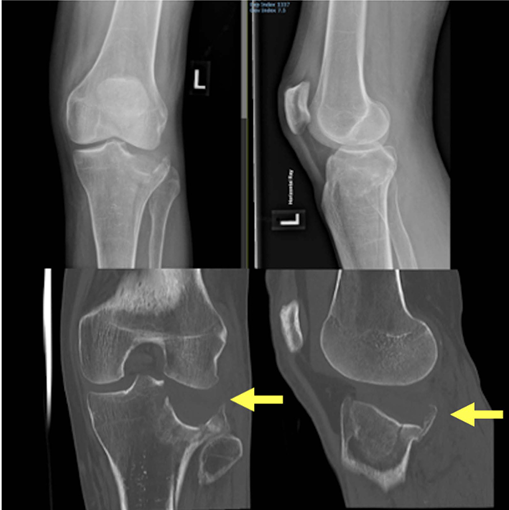

病例展示:后外侧劈裂塌陷骨折(Kfuri-Schatzker type II P型),A. 入院X线片,B. CT三维重建:清晰显示一个延长的后外侧劈裂骨块(星号标注)。此形态学分类有助于理解骨折的稳定性和手术策略。C. Carlson入路手术步骤:患者俯卧位,切口略偏内侧,与腓骨走向平行。神经显露:腓总神经(星号标注)位于浅筋膜下方、腓肠肌外侧头外侧,易于辨识。深层显露:将比目鱼肌从腓骨上剥离并抬起。将腘肌向内侧牵开。此时可显露外侧半月板(#号标注)。关节内观察:将外侧半月板向近端牵开后,可见后外侧缘的粉碎情况。